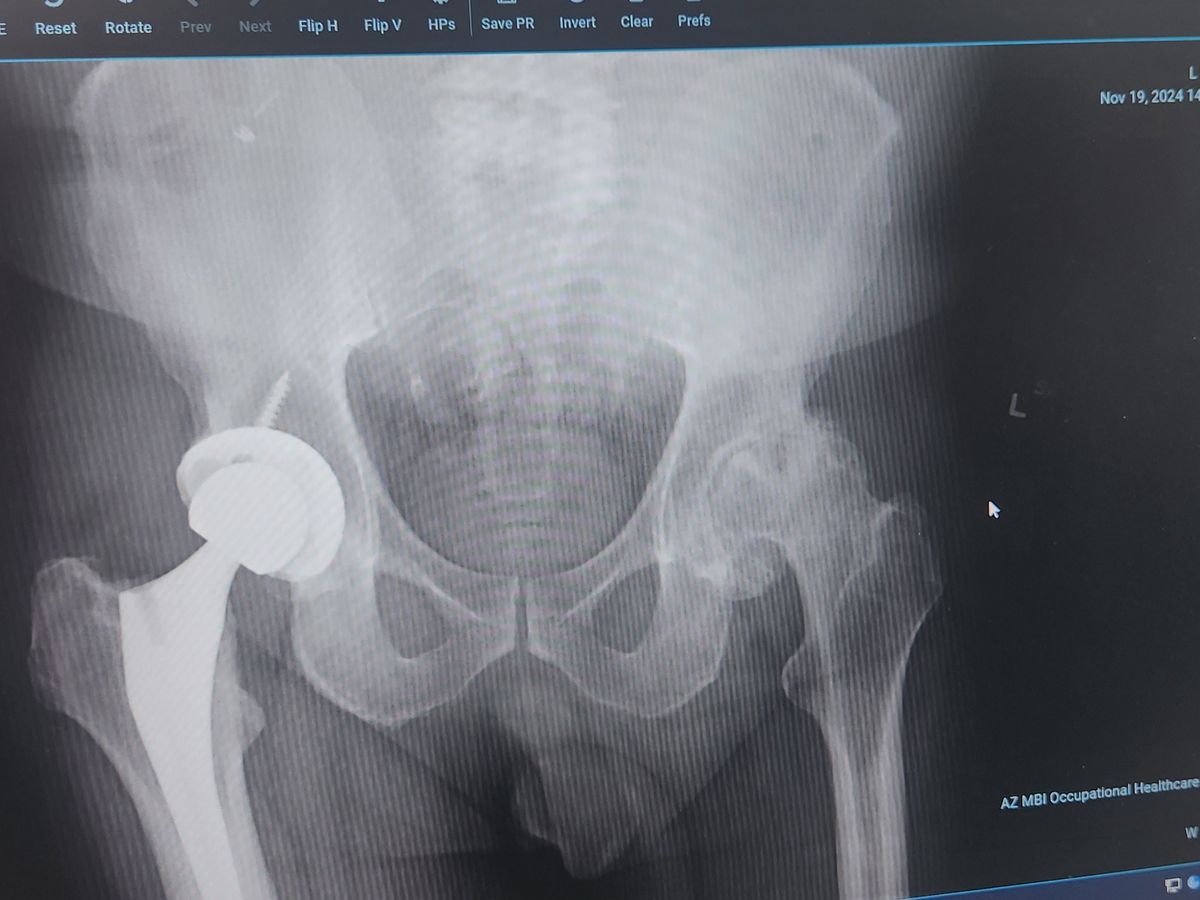

Hello! My name is Steve. I just turned 60 and am in need of a new hip and ive been diagnosed with prostate cancer. As you can see by the photo, I have already replaced my right hip. My left hip is worn out completely and causing me excruciating pain. I have recently been diagnosed with cancer and am currently going through all the scans and testing needed to find out the extent of the cancer. I injured my hip while working on 11/13, and my employer has denied my claim because the joint had arthritis in it, so they said it was a preexisting condition and not caused by work, even though I injured it while working.